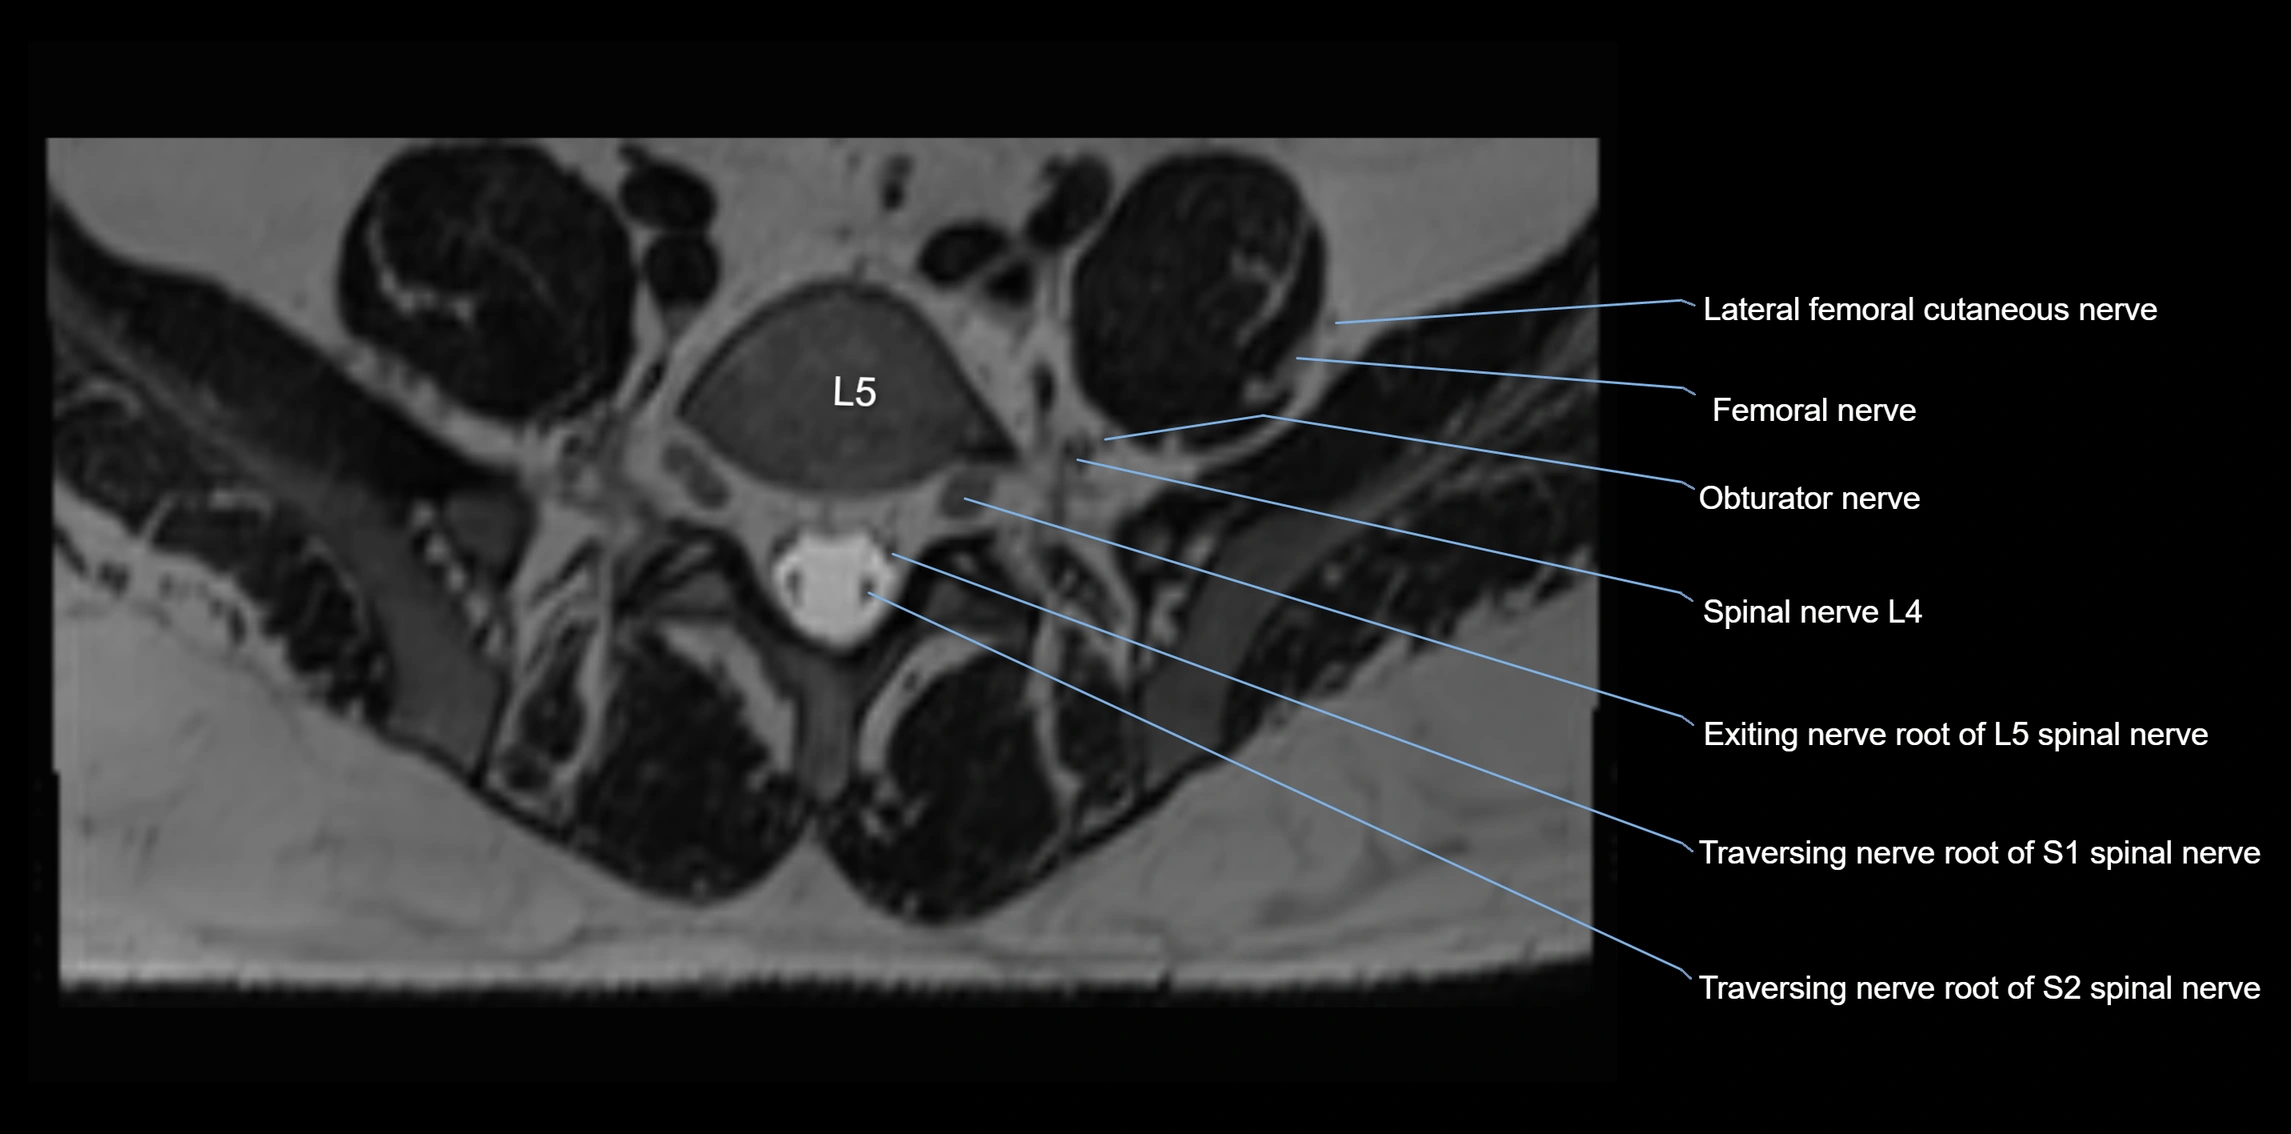

MRI image

image